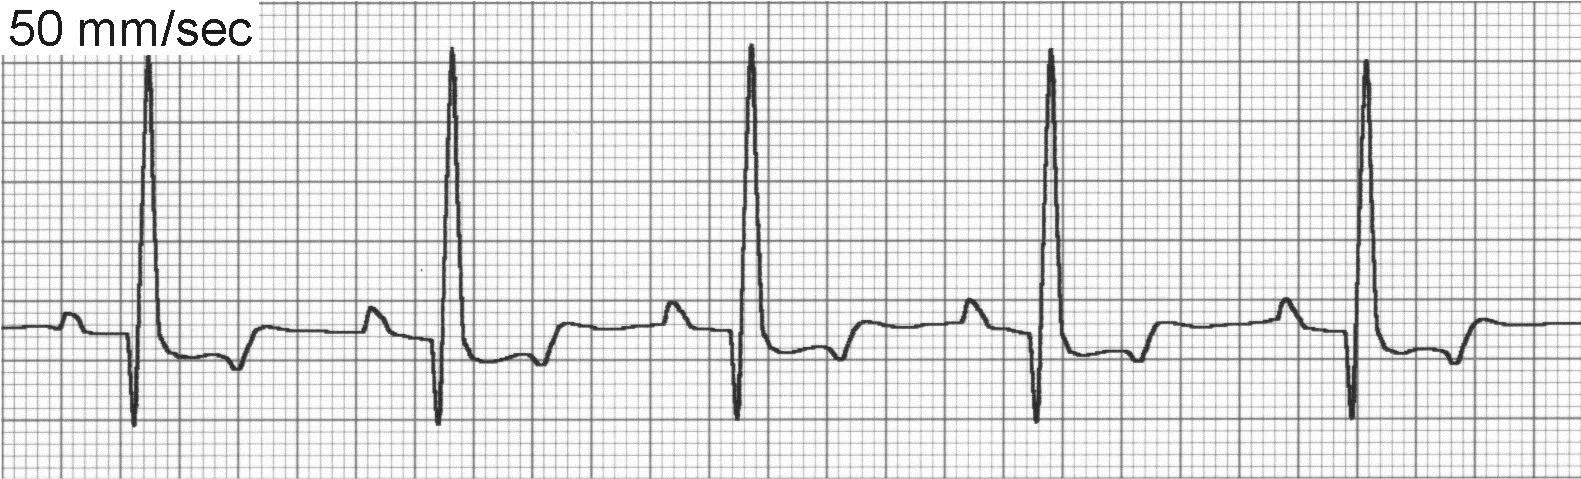

Sinus rhythm (Figure 2) maintains a regular underlying rhythm with P waves present for every QRS complex, QRS complexes present for every P wave, a relatively fixed PR interval, and SV QRS complexes. Sinus rhythm is normal for dogs and cats.

ECG of sinus rhythm